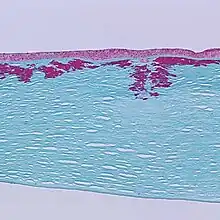

This gene encodes an RGD-containing protein that binds to type I, II and IV collagens. The RGD motif is found in many extracellular matrix proteins modulating cell adhesion and serves as a ligand recognition sequence for several integrins. This protein plays a role in cell-collagen interactions and may be involved in endochondrial bone formation in cartilage. The protein is induced by transforming growth factor-beta and acts to inhibit cell adhesion.[5]

Mutations of the gene cause several forms of corneal dystrophies.[7][8]